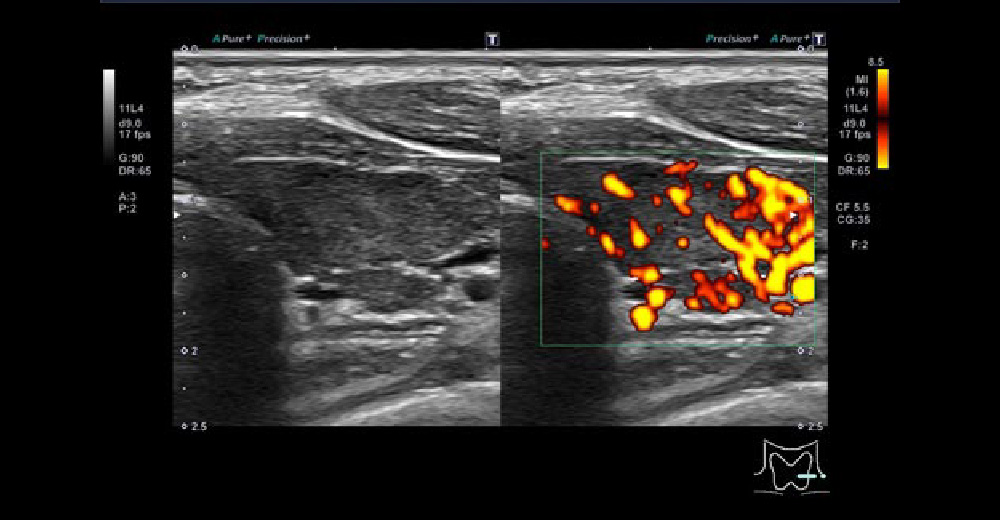

甲状腺乳頭がん切除術後10年以上の時を経て、左側頸部リンパ節に再発した症例です。

左総頚動脈周囲に、10mmを超えるリンパ節腫脹を認め、再手術に至りました。腫大したリンパ節は辺縁不整・内部不均一で、“丸まった”(縦横比が高い)形です。

術後は定期的な頸部エコーを行いましょう。エコーの時間は、約5-10分程度です。

甲状腺がん再発 甲状腺がん再発 甲状腺がん再発 甲状腺がん再発